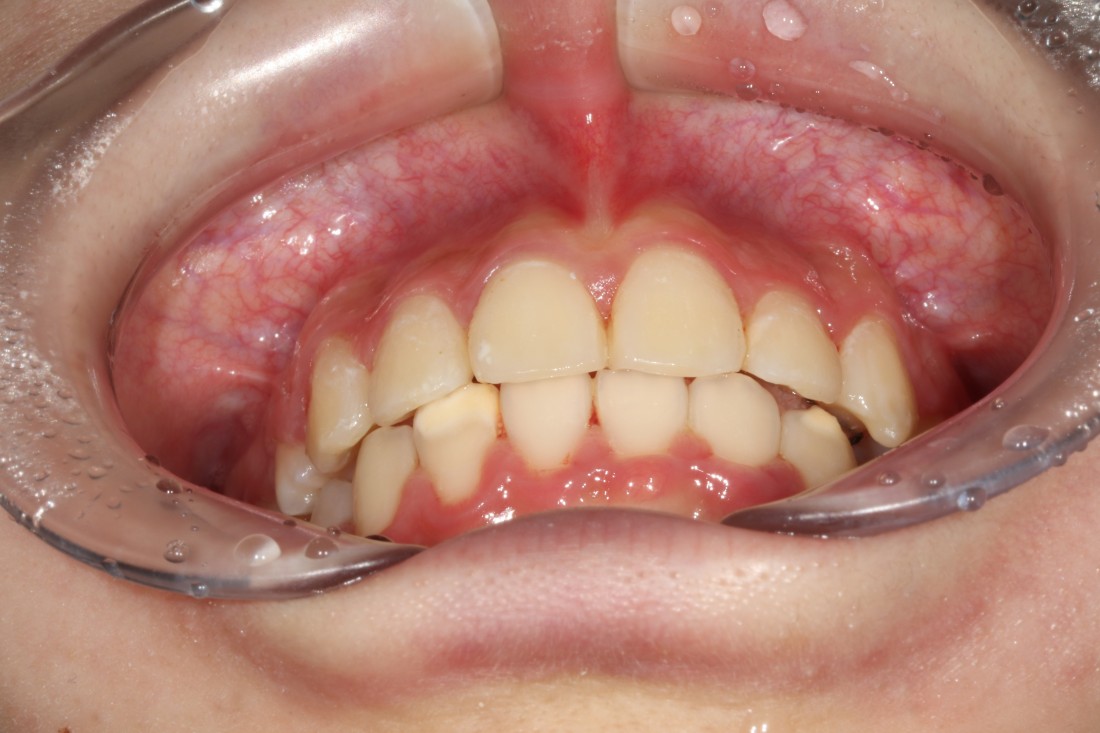

수많은 광주 치아교정 진짜 후기 사례를

공유하고 있는 광주 교정치과에서

성공적인 치아교정을 하실 수 있습니다.

환하고 밝은 미소를 완성하는

광주 교정치과의 교정진료입니다.